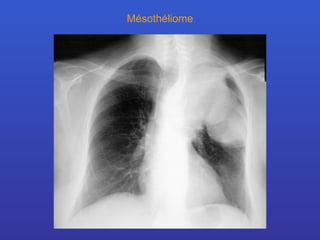

Mésothéliome